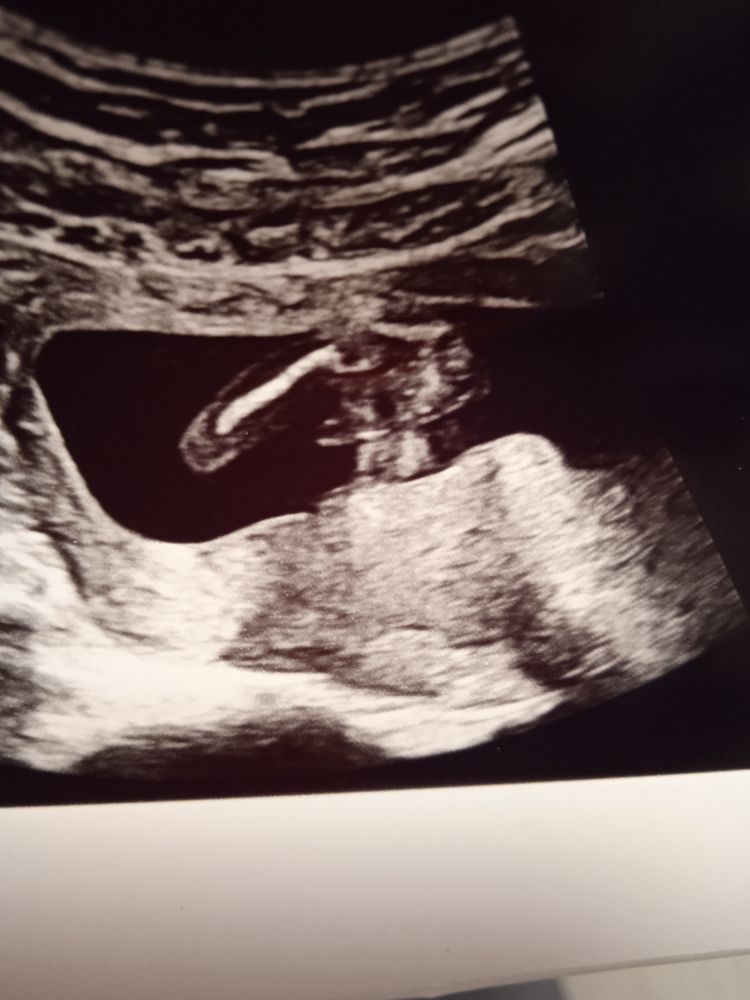

Узи 17 недель

Изображение Изображение Изображение Мальчик чуть больше 15 недель, на фото больше на девочку похоже🤗

Девочка) вон какой вареник

Мне кажется девочка🥰